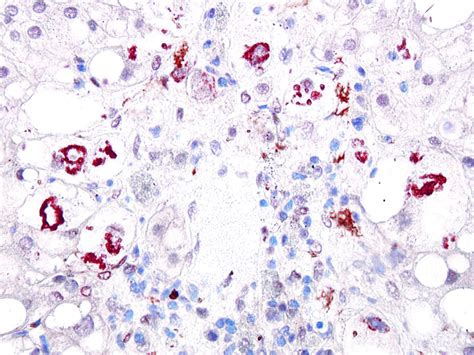

- mallory hyaline bodies

- mallory denk bodies liver histology

- mallory denk bodies liver

- mallory denk bodies histology

- mallory bodies histology

- mallory bodies liver biopsy